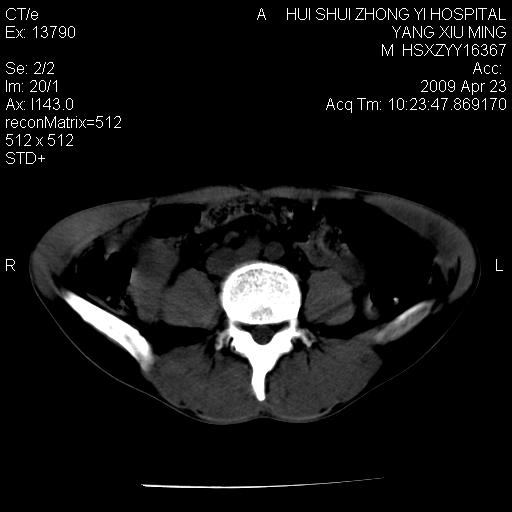

上腹部疼痛一月,呕吐10天,发现左侧颈部包快10天 胸部cr片未见明显异常。

腹膜后淋巴结增大,转移、淋巴瘤?胰腺增大,胰腺炎?占位?颈部考虑增大淋巴结。建议腹部增强扫描。

颈部及腹膜后淋巴瘤可能性大